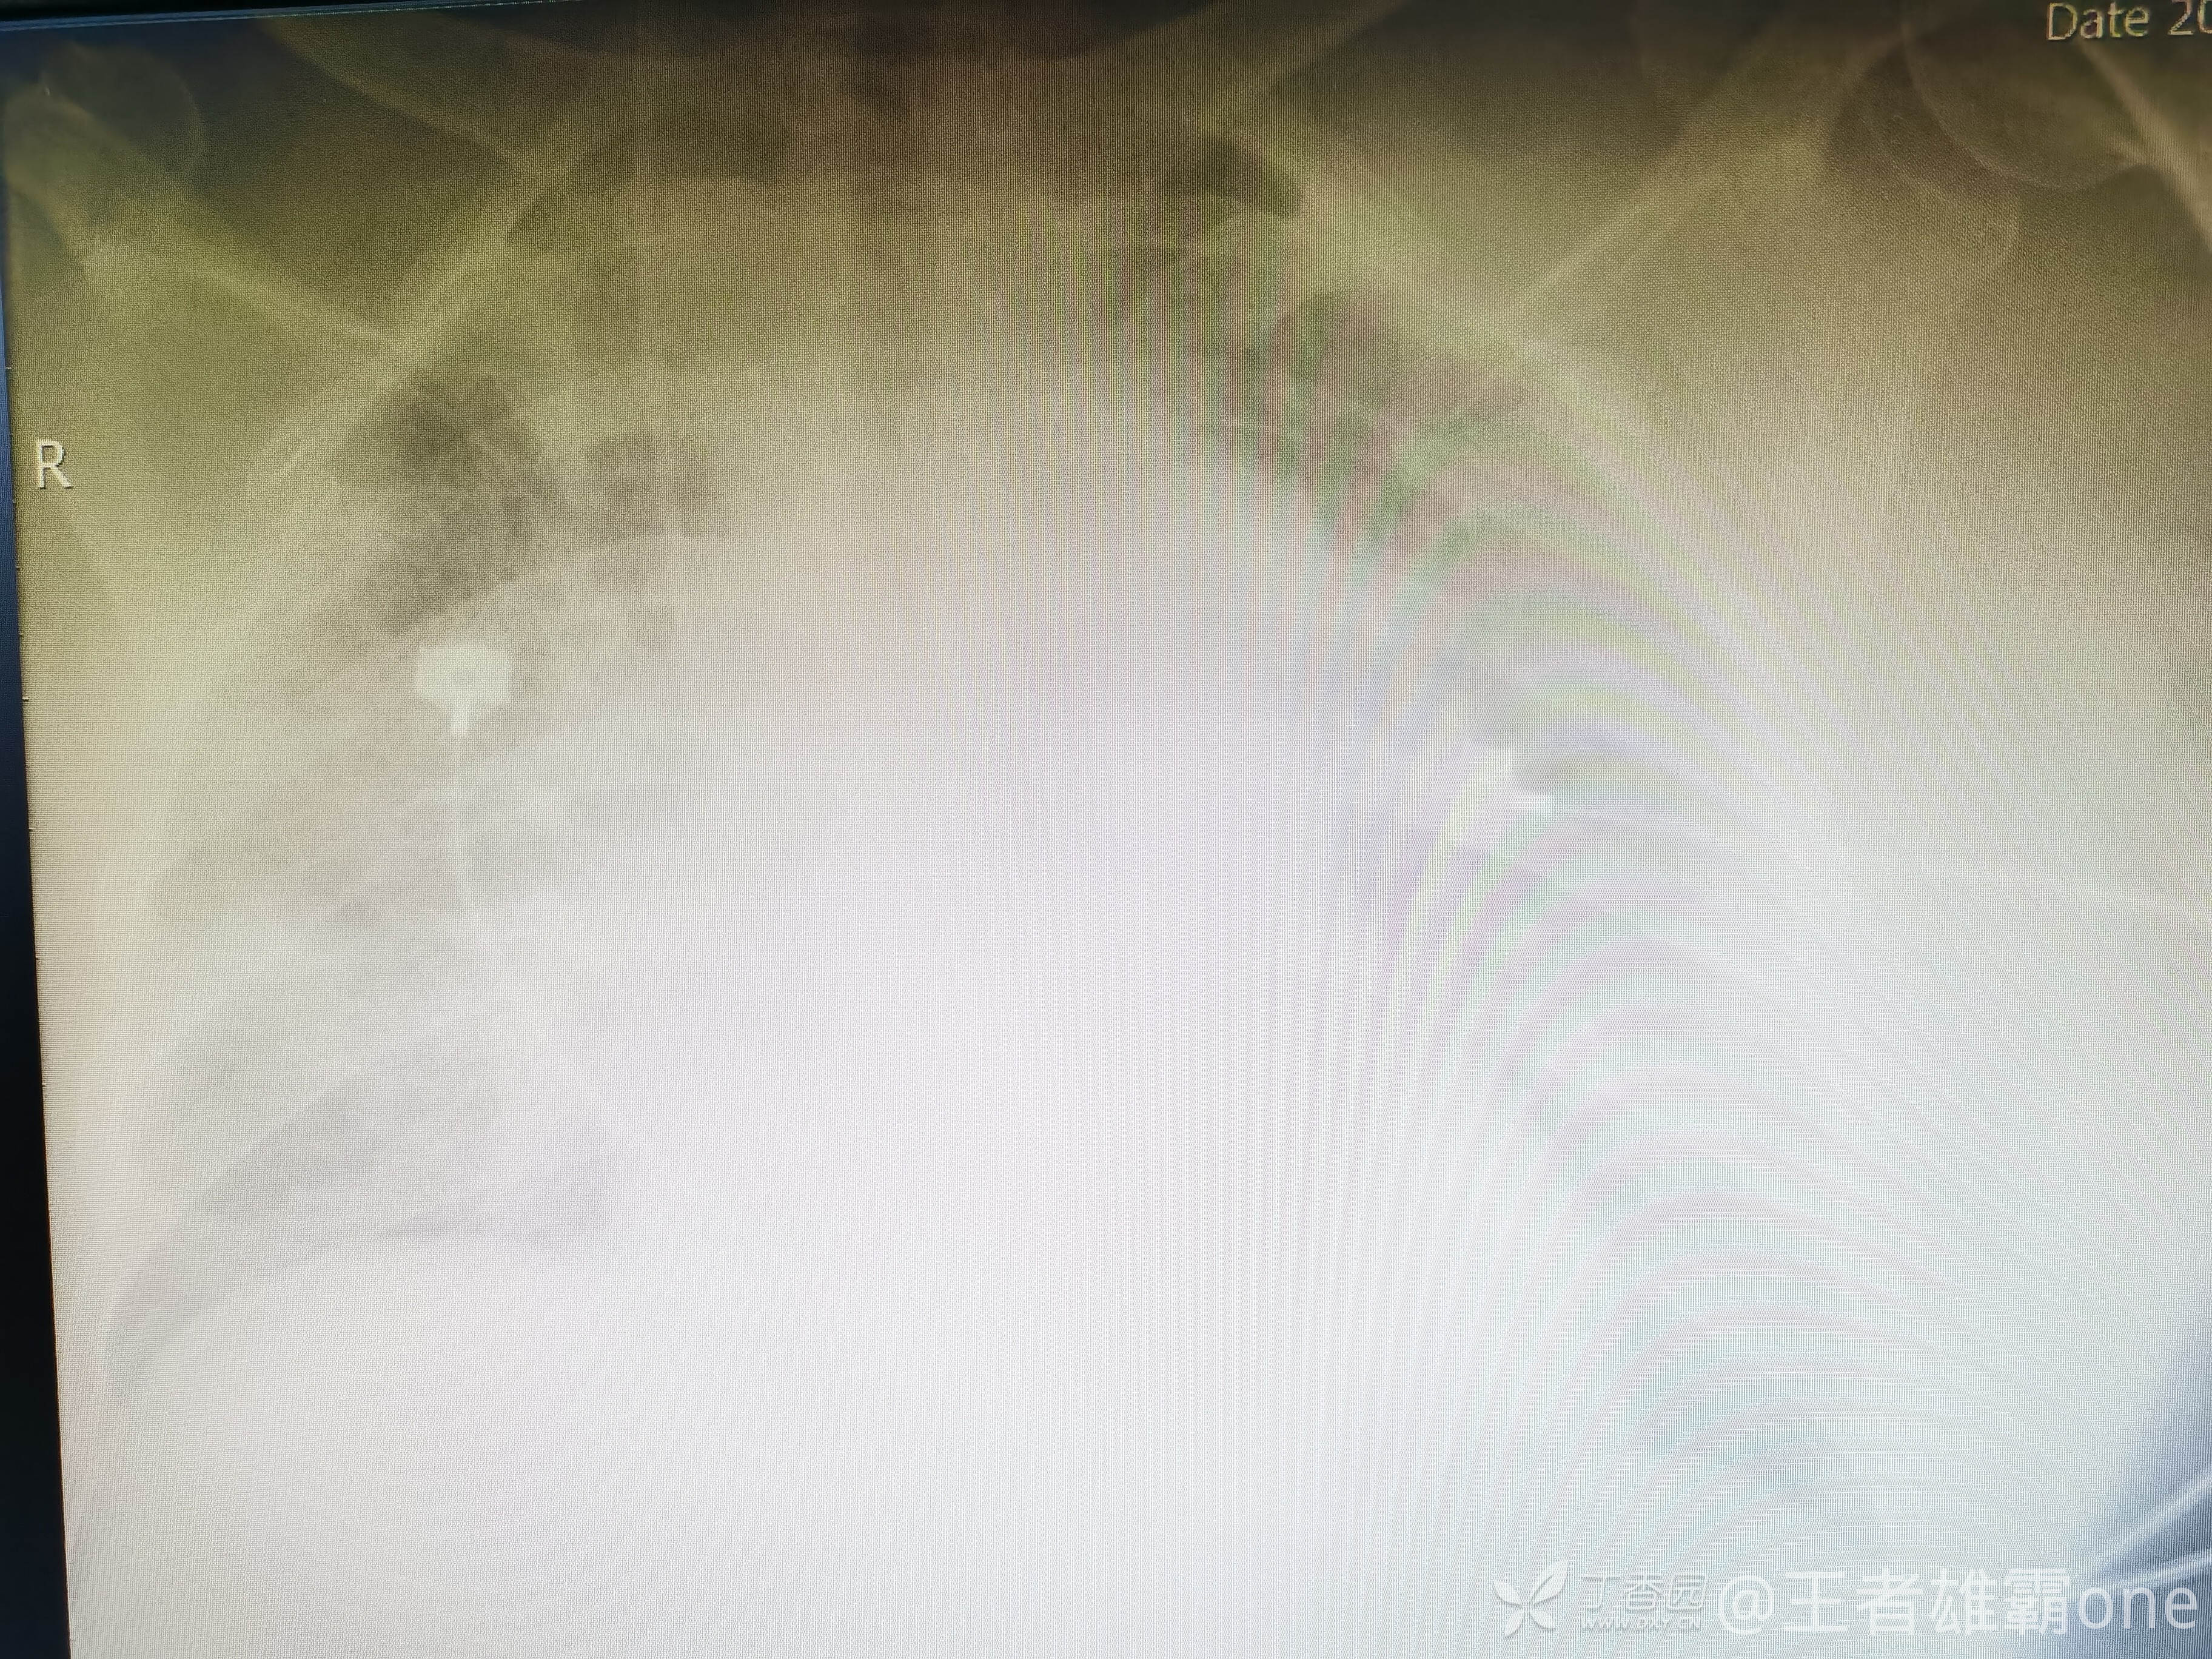

收入院治疗期间,患者神志清晰,体温、血压、心率等生命体征基本正常,到了凌晨02 :00左右出现呼吸明显急促(呼吸频率30次/分以上),改面罩高浓度吸氧,血气提示氧分压57mmHg,二氧化碳分压37mmHg,乳酸4.4mmol/L,血红蛋白10.4g/dL。查急诊胸片:

给予气管插管呼吸机通气。。